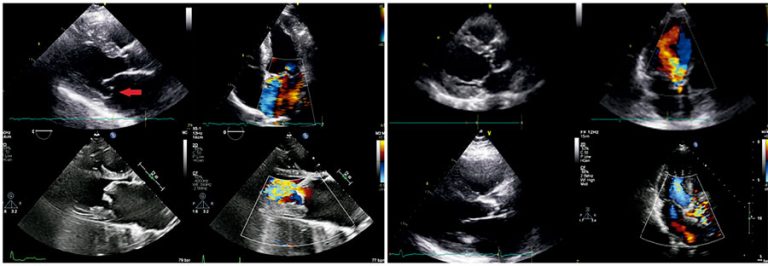

Proposing the ValvUS approach: integrating bedside tests and ultrasonography for severe valvular heart disease diagnosis

ABSTRACT Valvular heart disease is increasingly prevalent, and bedside confirmation or exclusion of severe disease is needed to enable a rapid and cost-effective diagnostic workup. The physical examination skills of clinicians are insufficient for accurate diagnosis, making complementary tests generally necessary. Despite being commonly requested, electrocardiography and chest radiography present low positive and negative likelihood ratios. Incipient studies involving artificial intelligence have shown promising opportunities to support the diagnosis. In addition, solid current evidence demonstrates that point-of-care ultrasound enhances bedside […]

Keywords: Aortic valve disease; Heart valve diseases; Mitral valve; Physical examination; Point-of-care systems; Point-of-care testing; Ultrasonography